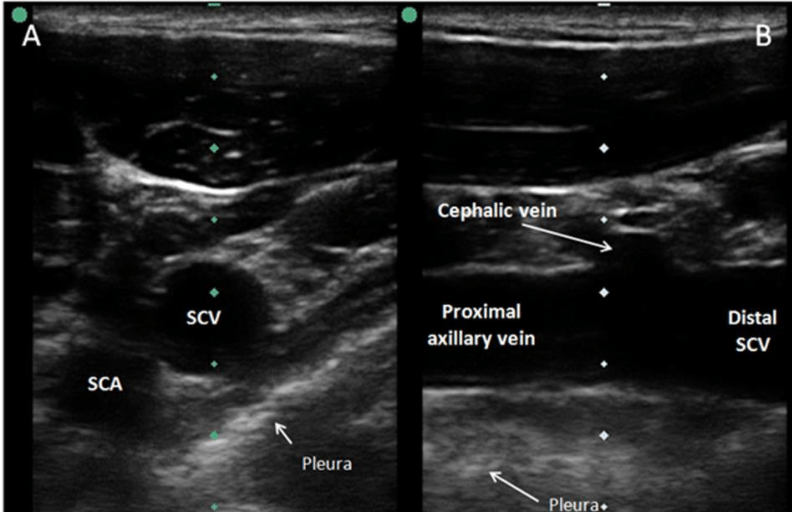

Subclavian vein(쇄골하 정맥)은 axillary vein(액와 정맥)의 근위부이며, 첫 번째 늑골의 lateral edge에서 medial 방향으로 brachiocephalic (innominate) vein(완두 정맥)으로 이어진다. 초음파는 뼈를 통과하지 못하므로 infraclavicular approach 시 axillary vein(distal subclavian vein)은 lateral clavicle의 화면상 아래쪽에서 보이게 된다.

Axillary vein은 첫 번째 늑골에서 teres major muscle로 주행하며 brachial vein(상완 정맥)이 되는데, axillary vein과 axillary artery의 상대적인 위치는 정상적인 변이가 매우 흔하므로, 이 위치에서 cannulation 시행을 할 때에는 반드시 초음파를 이용해야 한다.

Axillary vessels은 distal clavicle에서 short-axis (cross-section) view로 가장 잘 확인되는데, 이 위치에서 vessel이 가장 superficial 하게 위치하면서 diameter도 가장 크다. Long-axis(longitudinal) vies와 바늘 각도를 얕게 삽입하는 방법이 axillary vein cannulation 시 pleural 천자를 피할 수 있는 데 유용하다. 피부 삽입 부위는 화면과 transducer tip의 dimension 모두에 영향을 받는다. 즉, long-axis ultrasound guidance는 short-axis ultrasound guidance에 비해서 피부 사입 부위보다 몇 cm 멀리 떨어져 있을 수 있다.